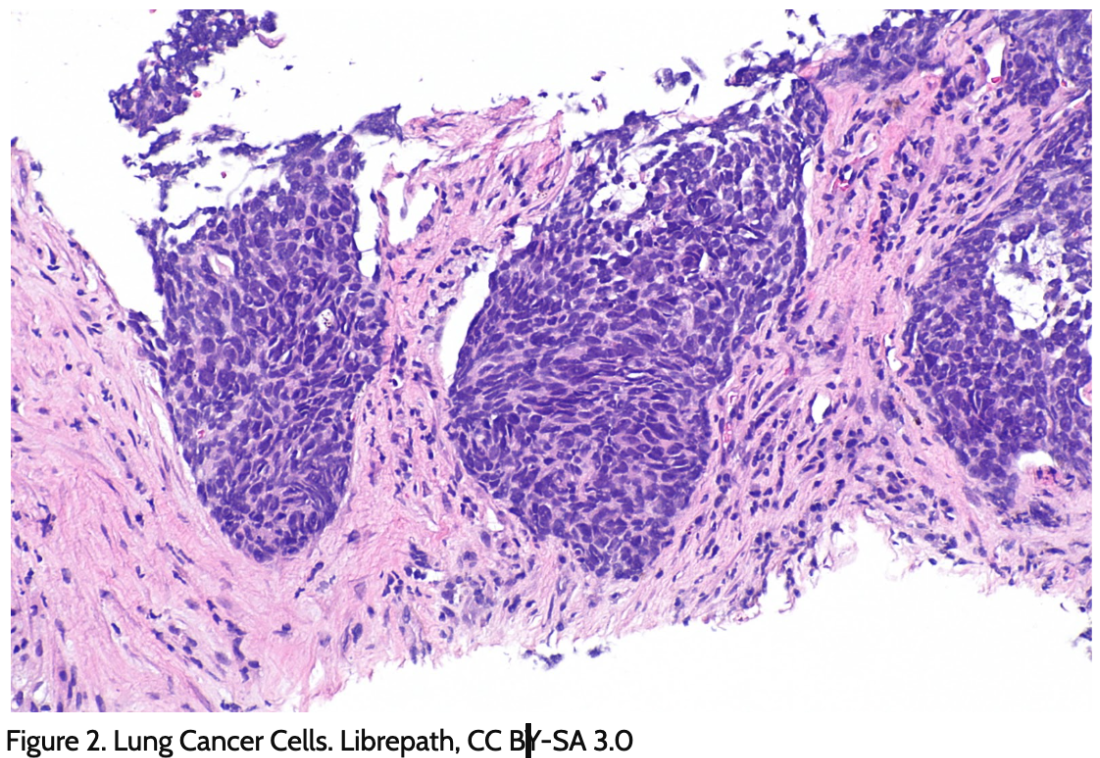

Who gets cancer and why? What can we do about it? This unit is designed to deepen student understanding of inheritance and variation of traits through an exploration of cancer as a phenomenon. In the first lesson set, students explore the genetic basis of cancer by investigating what cancer is and how mutations that can increase risk for cancer occur. While there are many genes implicated in cancer, the unit focuses on p53, a tumor suppressor gene that is involved in many different cancers. In Lesson Set 2, students investigate cancer caused by mutations that occur throughout our lifetimes, inherited mutations, and how the environment can cause mutations. In the third lesson set, students investigate additional factors that explain differences across the US in both instances of cancer and mortality, access and feasibility of treatment options, and explore the role of health navigator as a way to advocate for and help support friends and family that may be experiencing cancer.